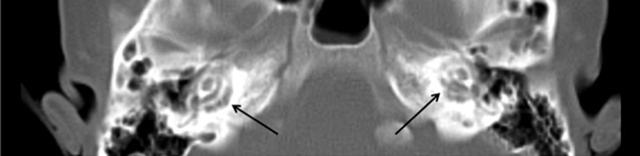

Figure 1

Axial CT-scan shows bilateral lucencies in the pericochlear bony otic capsule.